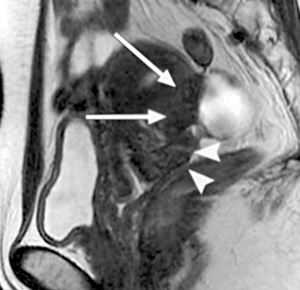

Επιπλέον, η μαγνητική τομογραφία κάποιες φορές συμπληρώνει τη διαγνωστική λαπαροσκόπηση, γιατί μπορεί να εντοπίσει εξωπεριτοναϊκές ενδομητριωσικές βλάβες ή εστίες κρυμμένες πίσω από στερρές και εκτεταμένες συμφύσεις, οι οποίες αποφράσσουν μερικώς ή πλήρως τον οπίσθιο δουγλάσειο. Τέλος, αποτελεί μια χρήσιμη μη επεμβατική μέθοδο παρακολούθησης των αποτελεσμάτων της φαρμακευτικής θεραπείας. Βρέθηκε πως η ύπαρξη σκιάς χαμηλής έντασης στις Τ2 ακολουθίες, πριν την έναρξη ή κατά τη διάρκεια της φαρμακευτικής θεραπείας των ενδομητριωμάτων, αποτελεί αρνητικό προγνωστικό παράγοντα. Αυτό οφείλεται στο γεγονός ότι το επιθήλιο της ενδομητριωσικής κύστης λεπτύνεται από την πίεση των προϊόντων του αίματος που συλλέγεται στο εσωτερικό της και το πυκνό αυτό υλικό δεν μπορεί να απορροφηθεί (εικόνα 4).(15)

Εικόνα 4. Ωοθηκικά ενδομητριώματα πριν και μετά τη θεραπεία με GnRH-a. Κεφαλή βέλους= δεξιά ωοθήκη (Α,Β). Εγκάρσιες Τ1 (Α) και T2(Β) τομές πριν την έναρξη της θεραπείας, όπου απεικονίζεται μια κύστη υψηλής έντασης (βέλη) που αντιπροσωπεύει ένα ενδομητρίωμα αριστερής ωοθήκης (Γ,Δ). Εγκάρσιες Τ1 και Τ2 τομές μετά τη θεραπεία με GnRH-a. Η κύστη είναι μικρότερη σε μέγεθος, αλλά έχει χαμηλής έντασης σήμα στις Τ2 τομές. Συνεπώς η ορμονική θεραπεία πρέπει να διακοπεί, καθώς η σκιά στο εσωτερικό της κύστης αποτελεί αρνητικό προγνωστικό δείκτη.